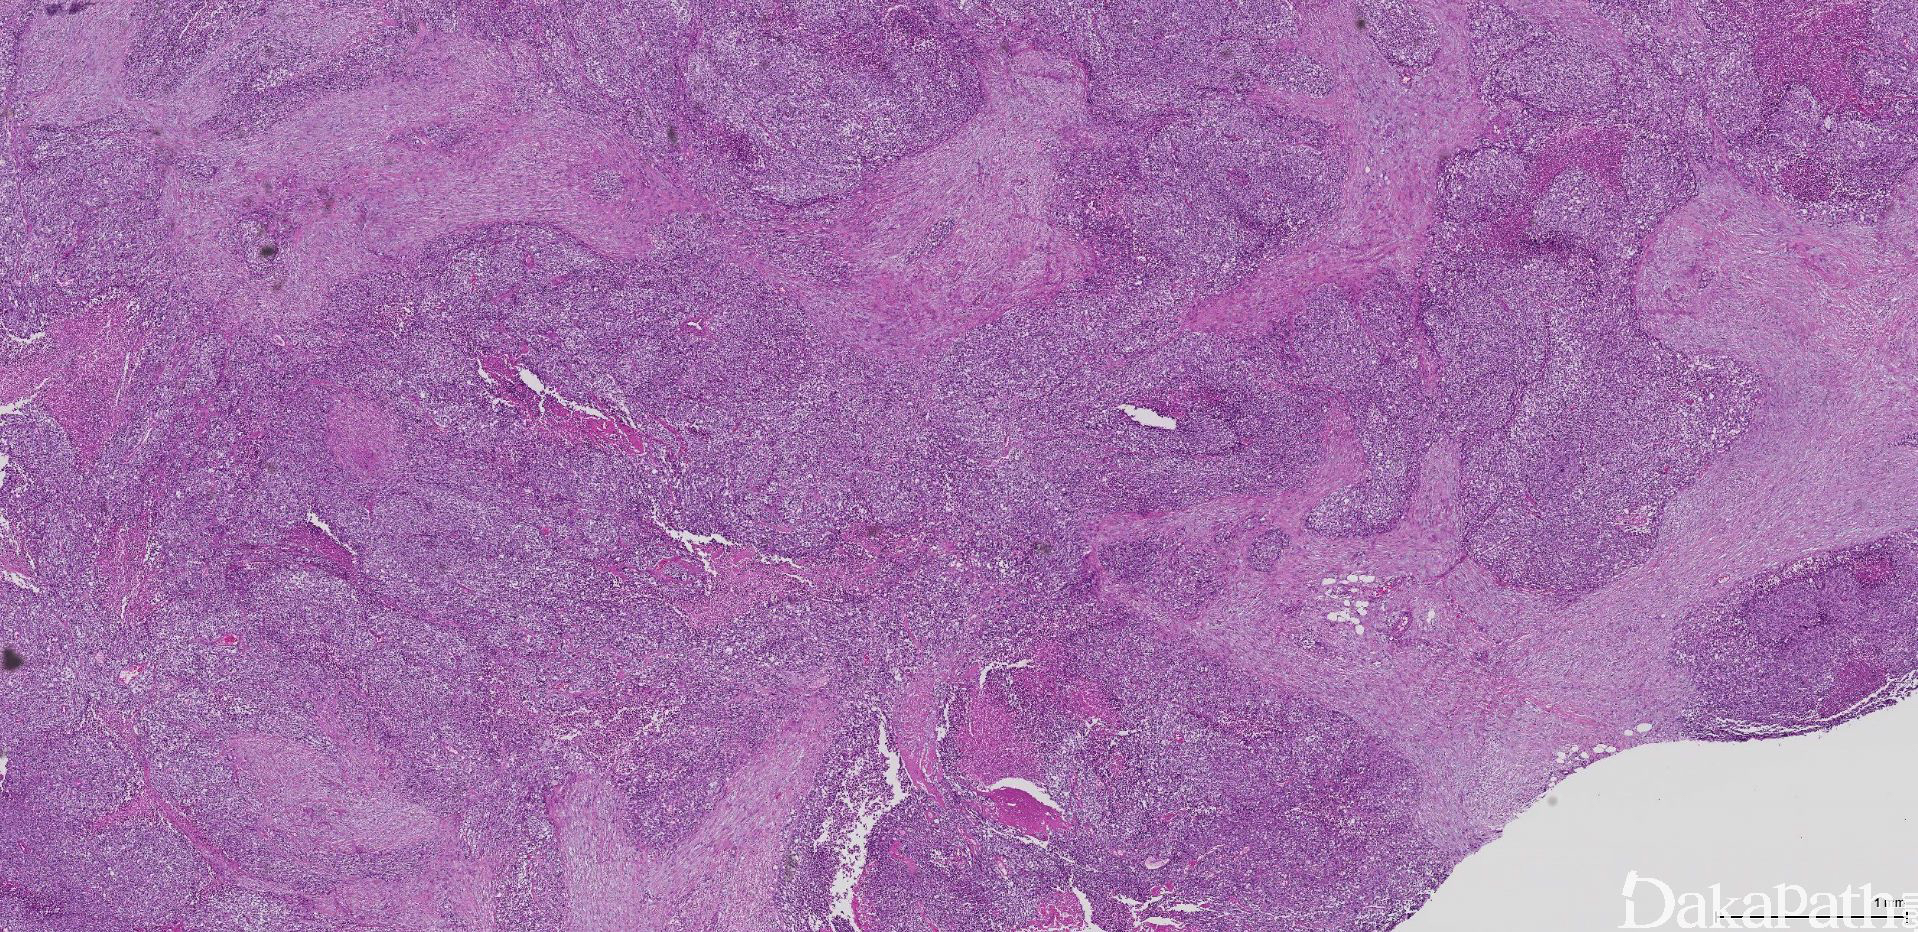

- 恶性小圆细胞肿瘤,瘤细胞排列紧密,并形成大小和形状不一的上皮样细胞巢,瘤细胞巢的周围和瘤细胞巢之间为大量增生的纤维结缔组织。

- 瘤细胞巢之间及其周围为大量增生的致密纤维结缔组织,可伴有玻璃(透明)样变性,有时可呈纤维黏液样,其内的梭形细胞多呈平行的束状排列,形态上类似纤维母细胞/肌纤维母细胞;